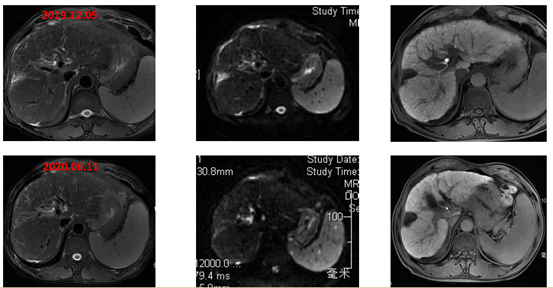

2019年12月5日(术后21个月,更改方案后2个月)进行影像学复查,疗效评价为达到PR,直至2020年6月11日(术后27个月)复查仍为PR状态,肿瘤标志物降至正常。

图片

图:影像学检查(第一行:2019-8-29,第二、三行:2019-12-5,第四行:2020-6-11)